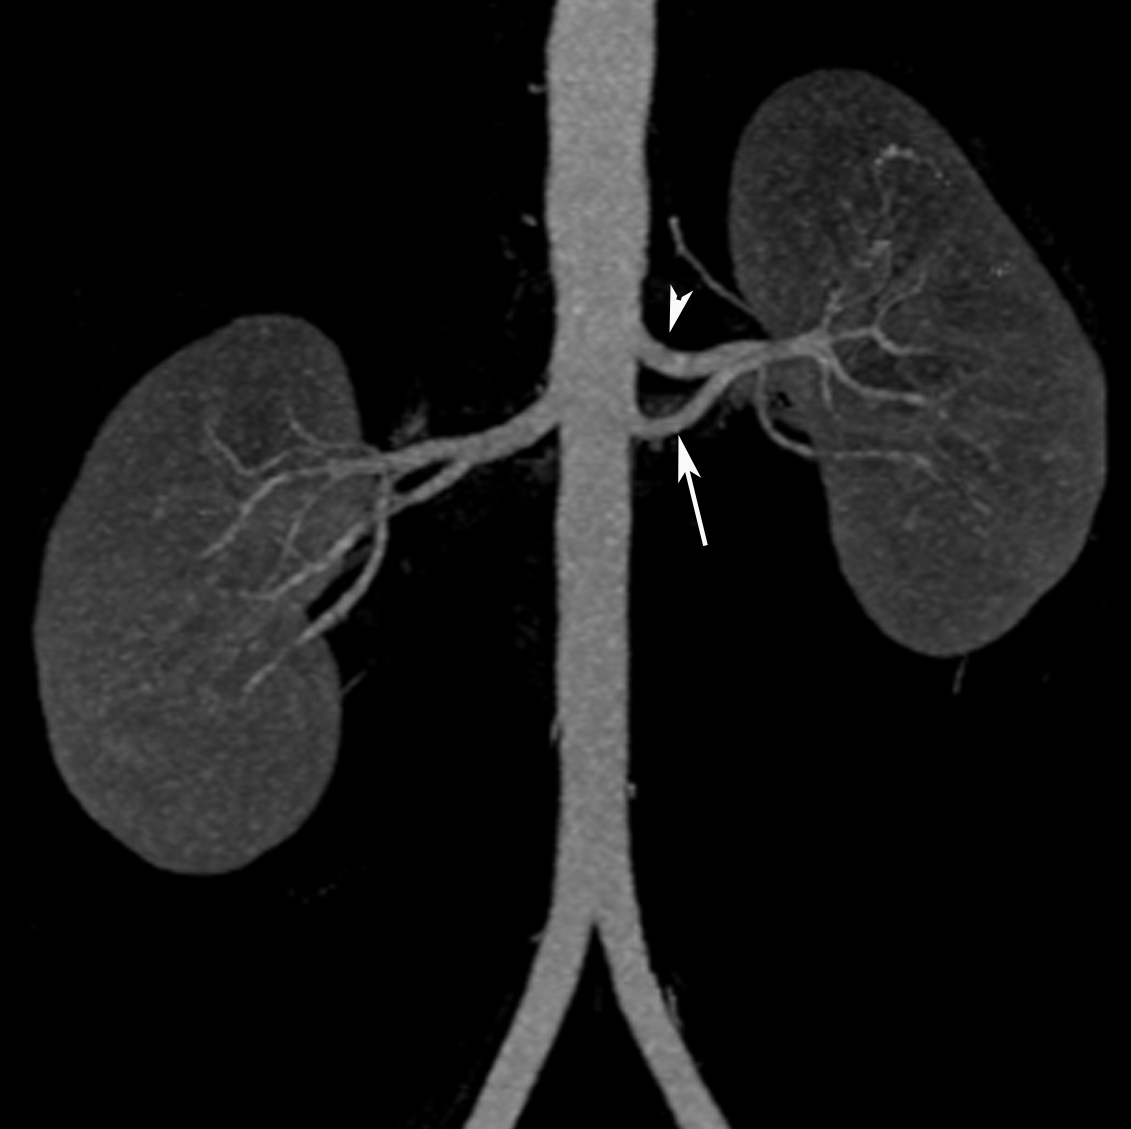

Left accessory renal artery arising below the main renal artery in a Accessory Renal Artery Meaning in 2008, the simplest definition of accessory renal artery was introduced. the renal arteries (ras) are important vessels that usually arise from the abdominal aorta and supply the kidneys; multiple (accessory, supernumerary) renal arteries and their position are common; an accessory renal artery (ara) is a vestigial structure that forms. Thus, these arteries play a. . Accessory Renal Artery Meaning.

Accessory renal artery and early branching in 50yearold female Accessory Renal Artery Meaning the renal arteries (ras) are important vessels that usually arise from the abdominal aorta and supply the kidneys; in 2008, the simplest definition of accessory renal artery was introduced. this article reports the incidence and variations of accessory renal arteries in 50 human cadaver kidneys. learn about accessory renal artery, a common variant of the renal. Accessory Renal Artery Meaning.